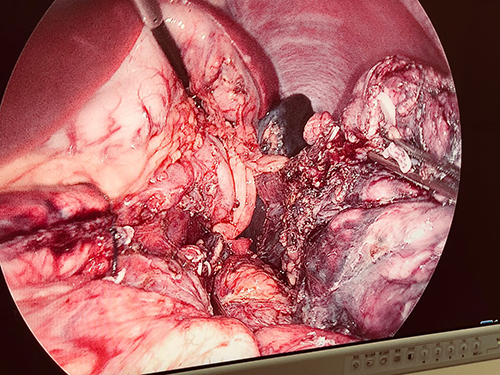

胰体尾实性假乳头状瘤---腹腔镜胰体脾切除